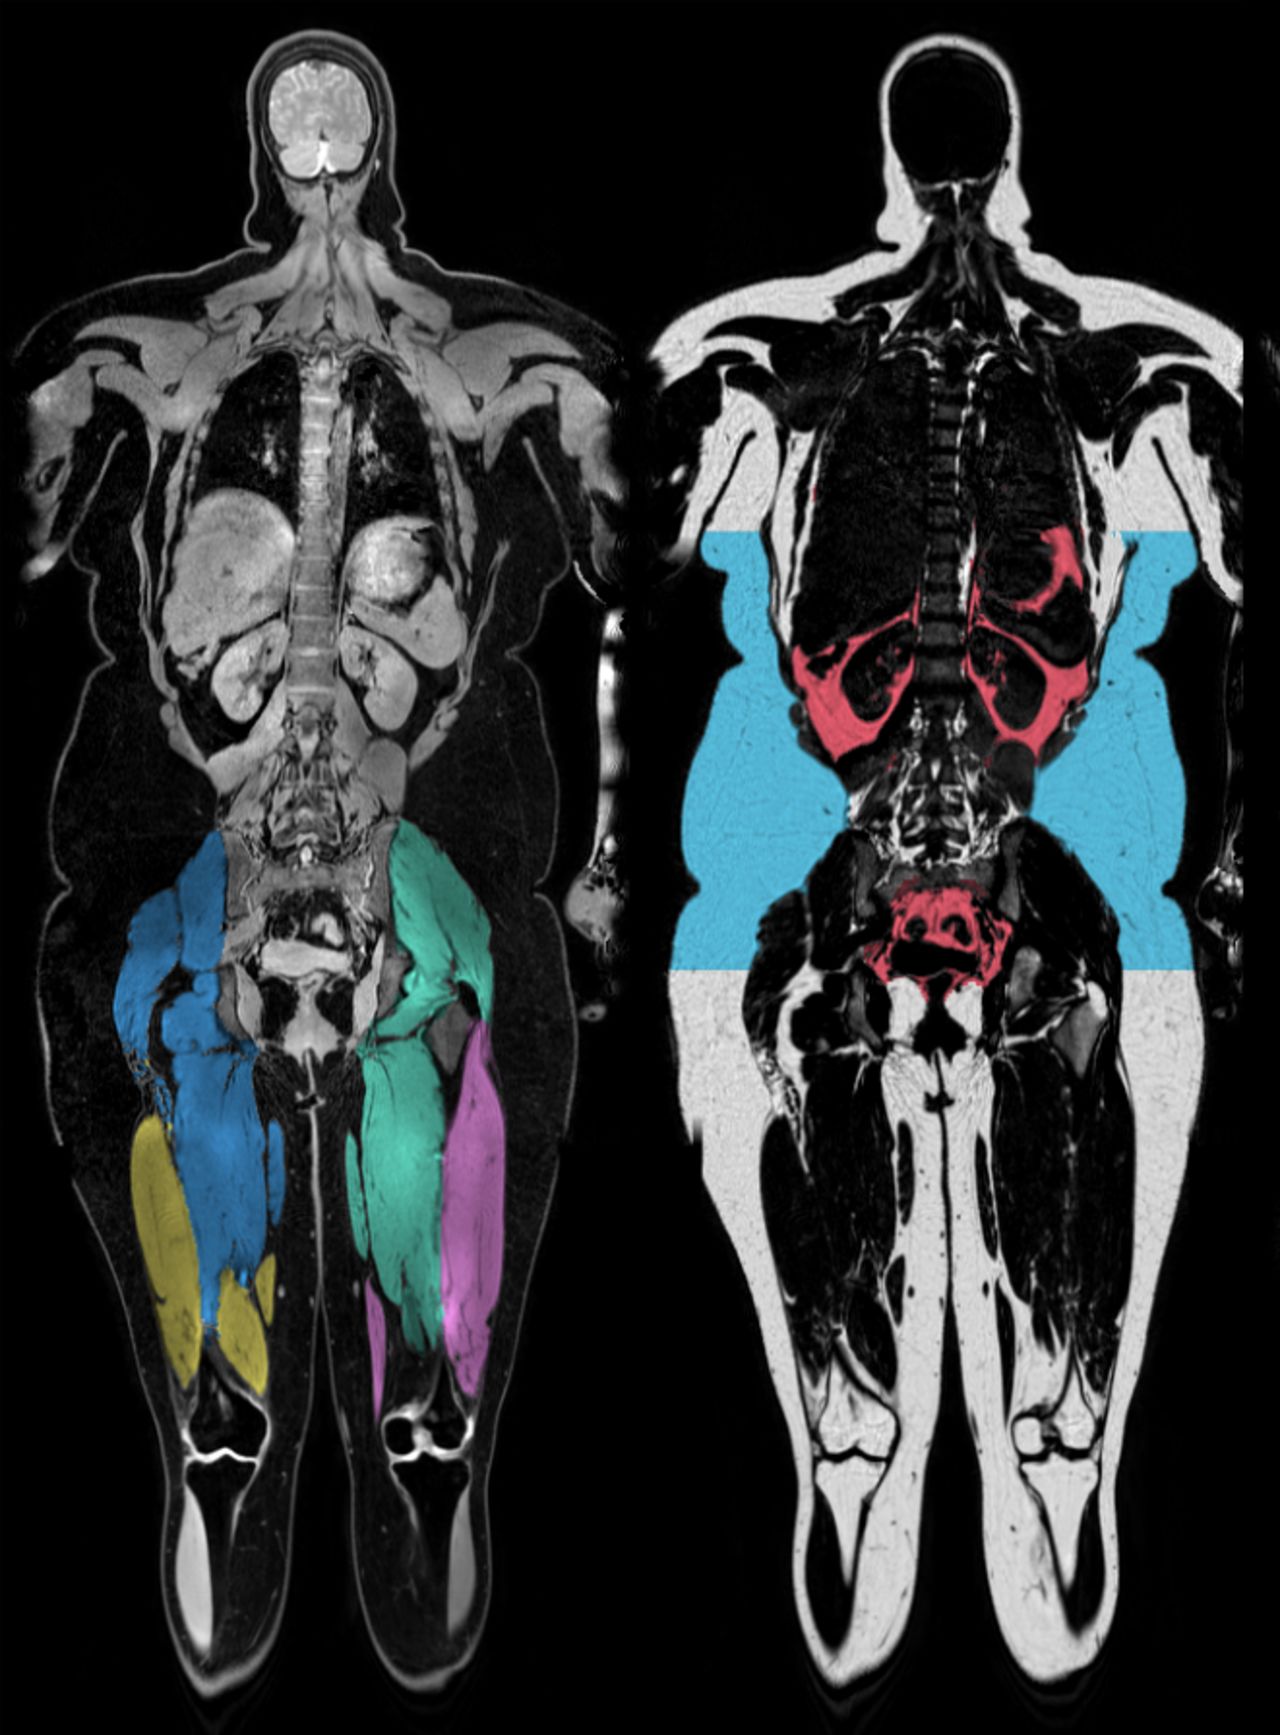

Body muscle and fat visualization. The left image shows segmented tight muscles and the right image shows belly fat where inner fat is red and subcutaneous fat is blue.

In line with previous reports we recently showed that that narcolepsy patients had more belly fat compared to their healthy controls (Fig. 1). However, we also found that they had lower ratio between inner fat and total belly fat indicating a relative increase of subcutaneous fat. This relationship between inner and subcutaneous fat has been associated with a lower risk for metabolic disease.